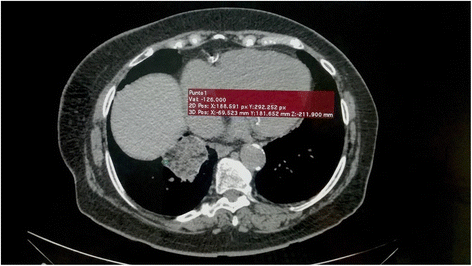

Laboratory findings demonstrated an increased CRP (31.5 mg/L, reference value 0.0 – 5.0 mg/L). After obtaining no relevant results, a follow up chest radiograph was ordered. It showed airspace consolidation as an irregular mass-like-lesion in the right lower lobe. The patient continued to be asymptomatic despite the presence of this mass. A thoracic computed tomographic (TCT) scan of the chest was ordered. This showed a pulmonary consolidation of 5.0 × 4.5 cm in the posterior basal segment of the lower lobe of the right lung, containing negative density regions measuring between −130 HU and −61 HU, indicative of intrapulmonary lipid (Fig. 1). Focal ground-glass opacities were observed in the periphery and scattered ground glass opacities bilaterally, which are suggestive of pneumonitis. We recommended that the patient stop using Vicks VapoRub®, and prescribed intranasal corticosteroids for her rhinitis.

Twenty-six months after stopping daily mentholated ointment application a follow-up TCT and CRP was ordered. The pulmonary consolidation described above was still apparent, but the bilateral scattered ground glass opacities had diminished and the size of the mass had decreased by 0.5 cm in each dimension (4.5 × 4.0 cm) (Fig. 2). CRP was in reference value (2.03 mg/L)